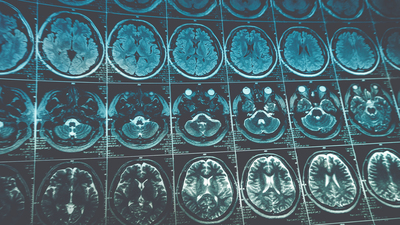

İngiltere'deki Imperial College London, Almanya'daki Münih Teknik Üniversitesi ve İskoçya'daki Edinburgh Üniversitesinden bilim insanları, yeni yapay zeka yazılımını, inme geçirme zamanı bilinen 800 hastanın beyin taraması üstünde geliştirdi.

Geliştirdikleri yapay zeka modelini yaklaşık 2 bin hastadan alınan verilerde de test eden araştırmacılar, bu yazılımın standart bir görsel yöntem kullanımına kıyasla inme geçirme zamanını belirlemede 2 kat daha doğru sonuç verdiğini belirledi.

Araştırmacılar yazılımın, beyin taramasında ilgili alanı otomatik olarak çıkarmanın yanı sıra, tanımlanan lezyonları analiz ederek inme geçirilen zamanı tahmin edebildiğini tespit etti.

Araştırmacılar, yeni yapay zeka yazılımı kullanılarak yapılan taramaların doku gibi ek özellikler içermesi ve lezyonlardaki varyasyonları hesaba katmasının daha önce kullanılan tarama yöntemlerine kıyasla daha iyi sonuç alınmasında etkili olduğunu belirtti.